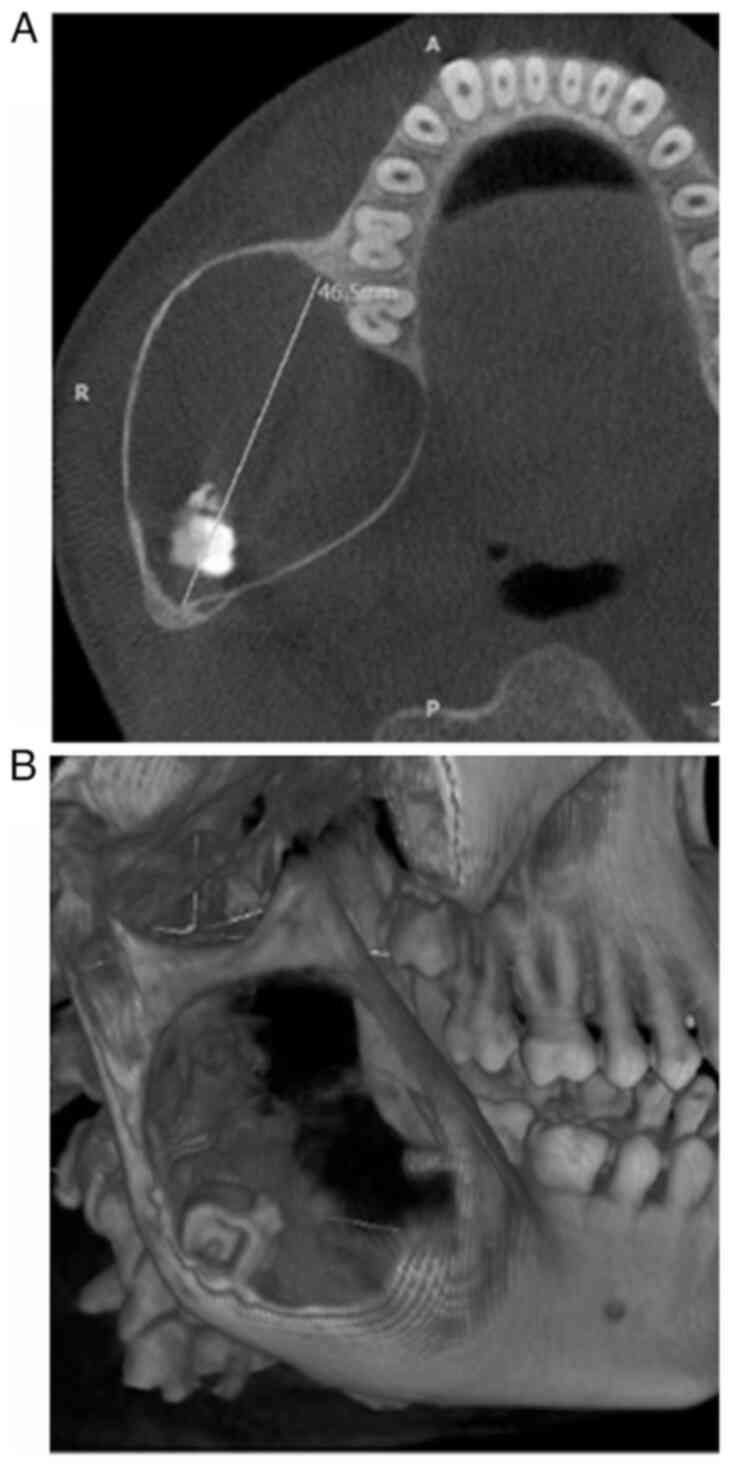

Cone-beam computed tomography was used to identify a predominantly hypodense area of unilocular nature. This area involved the right body, angle and ramus of the mandible, with a thin corticated margin. The area extended anteriorly from the lower right first molar region to the posterior border of the ramus. The dimensions of this area were 46.5 mm anteroposteriorly, 38.3 mm mediolaterally, and 53.8 mm superioinferiorly, as illustrated in Fig. 1A. An apically displaced third molar in the right mandibular region near the angle of the mandible was observed, in association with calcification flecks (Fig. 1B). The presence of a bony crypt related to the third molar was not observed. However, both the lingual and buccal cortical plates appeared to be attenuated and displayed an obvious expansion without any discernible disruption of continuity.

Figure 1

(A) Computed tomography image illustrating the anteroposterior expansion of the lesion, extending anteriorly from the lower right first molar region to the posterior border of the ramus. A, anterior; R, right; P, posterior. (B) An apically displaced third molar in the right mandibular region near the angle of the mandible.